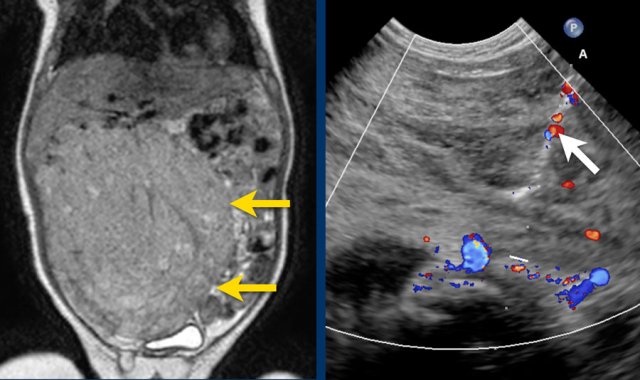

Ultrasound of a fifteen-month-old boy, who was first suspected of having a tumor in the left kidney.

Ultrasound shows a mass adjacent to the medial upper pole of the left kidney. It seems to be separate from the kidney. The mass is very inhomogeneous and has multiple calcifications.

These findings are more compatible with a neuroblastoma than a nephroblastoma.

The extent of the tumor is well appreciated on a 3D axial T2 weighted TSE series.

The left kidney is compressed and displaced caudally.

Para-aortal lymph node metastases are present (small yellow arrow).

The origins of the celiac trunc and superior mesenteric artery are encased by tumor (arrowhead).

The inferior caval vein is lifted anteriorly (green arrow).

Bilateral dorsal atelectasis is often seen on the MRI, because the examination is done under anesthesia.

The MRI is of a nine-months-old girl with a tumor in the left abdomen. The MRI shows a tumor of the left adrenal gland, partially solid, partially cystic. Multiple liver metastases are present.

The tumor was biopsied. There was constant blood loss through the guiding needle. At the end of the procedure two gelatin foam plugs were placed (echogenic stripes (arrows).